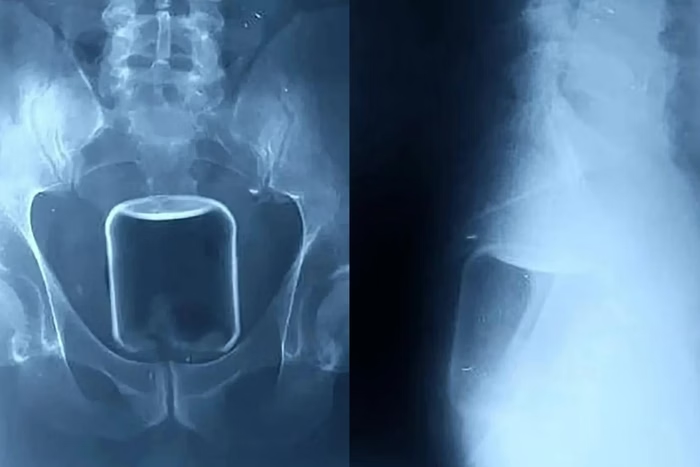

Em Nizhny Novgorod, na Rússia, um homem passou por uma cirurgia de alto risco para a remoção de um copo de vidro inserido no intestino pelo ânus durante um ato sexual. Além do copo, os médicos também retiraram um preservativo e lubrificante. O procedimento foi necessário para evitar complicações graves, como hemorragias fatais ou danos irreparáveis aos órgãos internos.

O paciente precisou ser submetido a uma intervenção cirúrgica após exames indicarem que o copo estava alojado na parte superior do reto e avançava em direção ao intestino superior. Segundo os médicos responsáveis, caso o frasco tivesse se quebrado dentro do organismo, as consequências poderiam ter sido fatais devido à possibilidade de hemorragias severas.